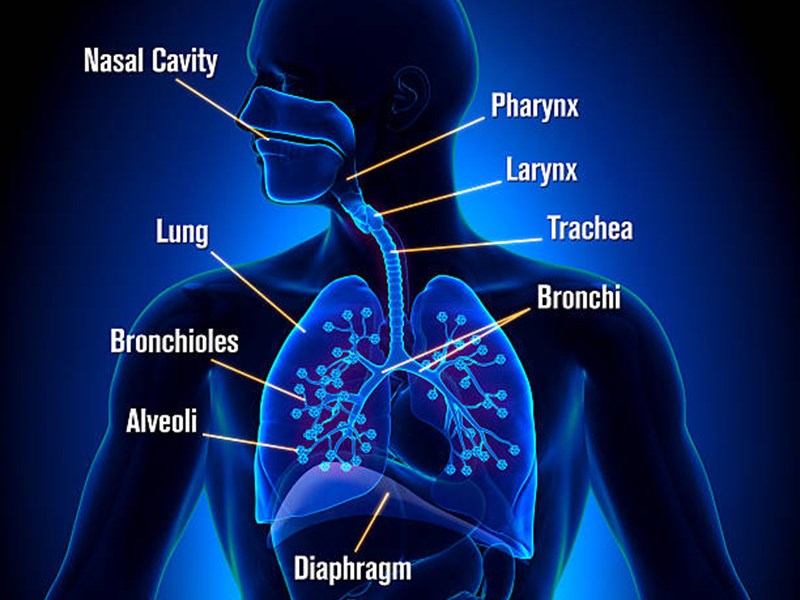

Respiratory System

Respiratory system: It is the anatomical system of an organism that introduces respiratory gases to the interior and performs gas exchange. In humans and other mammals, the anatomical features of the respiratory system include airways, lungs, and the respiratory muscles

Anatomy

The body needs energy for survival. Most of this energy can only be produced in the presence of oxygen. The waste product of this energy production is carbon dioxide. The respiratory system is responsible for supplying oxygen and the excretion of carbon dioxide.

The respiratory system consists of the following organs:

· Nose

· Pharynx

· Larynx

· Trachea

· Bronchi

· Bronchioles

· Lungs

· Muscles – intercostal muscles and diaphragm